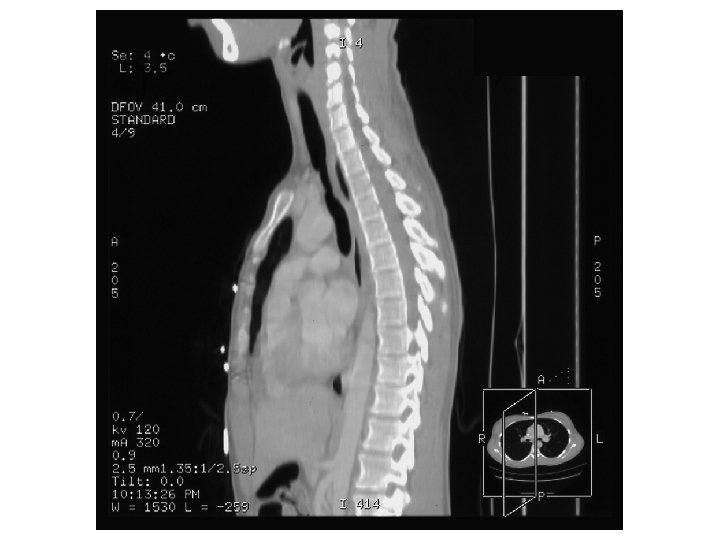

Case History 22 y. o. female with history of schizophrenia, recently intubated for 1 week for drug overdose. Patient developed chronic cough, great difficulty breathing and wheezing after extubation.

Findings and Differentials Pulmonary Parenchymal Findings: Nodules and branching linear opacities (aka “tree-in-bud”) in both lower lobes Differentials for tree-in-bud: • Infection: Mycobacterial, bronchopneumonia, viral, fungal, aspiration • Bronchial disease: Bronchitis/ bronchiolitis, diffuse panbronchiolitis • Congenital: Cystic Fibrosis, Dyskinetic Cilia Syndrome • Immunologic: ABPA • Lymphatic disease: Lymphangitis carcinomatosa, sarcoid, Langerhans Histiocytosis • Mets: Hematogenous mets (very rare)

Findings and Differentials Tracheal Findings: Focal tracheal narrowing Differentials for tracheal narrowing: • Traumatic injury/ iatrogenic (e. g. endotracheal intubation) • Congenital tracheal stenosis • Infection: fungal, TB • Inflammatory: sarcoidosis, amyloidosis, relapsing polychondritis • Neoplasm: squamous cell carcinoma, chondroma, fibroma, papilloma

Discussion In both lower lobes, there are multiple small nodules and branching linear opacities in a centrilobular distribution, also described as a “tree-in-bud” pattern. This pattern represents bronchiolar dilatation and filling by mucus, pus, or fluid, resembling a branching tree with buds at the tips of the branches. This finding is indicative of airway disease, and is particularly common in endobronchial spread of infection with mycobacteria (such as TB) and viruses (such as RSV and adenovirus). Other causes include cystic fibrosis, diffuse panbronchiolitis, and chronic airway infection due to asthma, chronic bronchitis, and bronchiectasis. Focal tracheal stenosis may be caused by a number of conditions, the most common of which is intubation-related injury. Overinflation of the cuff can produce blood flow obstruction, leading to inflammation and erosion of the tracheal mucosa and later, necrosis and destruction. Cuff strictures can occur as little as 36 hours after intubation and usually become symptomatic an average of 5 weeks later. The other causes of narrowing (congenital, infectious, inflammatory, and neoplastic) are much less common. Prior to the patient’s illness, she had no history of tracheal anomaly. The patient developed stridor after prolonged intubation, which would make intubation the most plausible etiology for the imaging findings. References: AJR 1998; Collins J, et al. CT patterns of bronchiolar disease: What is “Tree-in-Bud”? 171: 365370 Mc. Loud T. Thoracic Radiology: The Requisites 1998 Baylor College of Medicine Dept. of Otorhinolaryngology Grand Rounds Archives 1991; Eicher S. Benign Tracheal Stenosis Chest Surg Clin N Am. 2003; Wain J. Postintubation tracheal stenosis. 13(2): 231 -46

Diagnosis 1) Tree-in-bud: Currently unknown. Negative for AFB, PCP, or fungal infection. Respiratory cultures have been negative, but the patient was incompletely treated with antibotics. Aspiration is therefore most likely. 2) Tracheal stenosis: Iatrogenic related to recent intubation. She has been treated with bronchoscopically guided tracheal dilatation x 2. Due to her young age, her physicians are opting for dilatation of the trachea rather than stent placements.